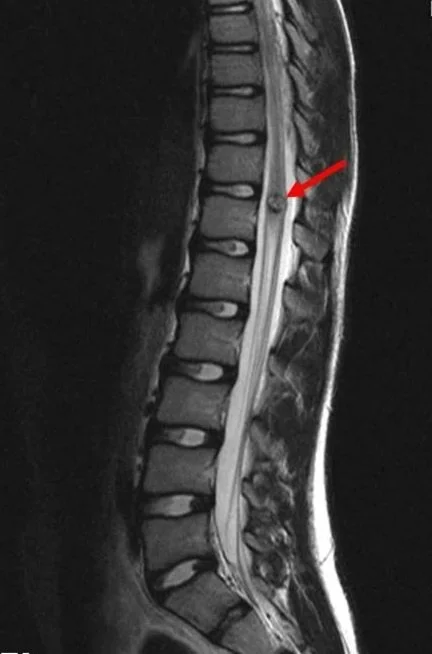

A spinal cord stroke—also referred to as a spinal cord infarction—is a sudden disruption of blood flow to the spinal cord, leading to tissue damage and potentially permanent loss of function. Though it’s often less familiar than strokes affecting the brain, it is no less serious and requires urgent medical attention.

After extensive and repeated tests and scans, it was determined that Olivia experienced an Ischemic Spinal Cord Stoke of unknown etiology. This means that there was a blood clot in Olivia’s spine that blocked flow to her spinal cord and there was no known reason for it to have happened. It was not foreseen, nor could it have been prevented.